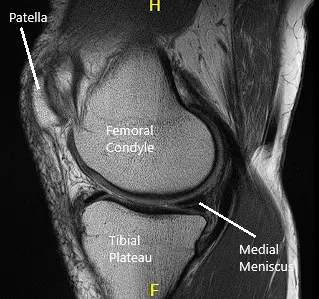

La resonancia magnética de la rodilla izquierda sugirió desgarro del cuerno posterior y de la unión del cuerno posterior/segmento del cuerpo en el menisco medial, con una leve extrusión meniscal hacia la canaleta medial y una condromalacia rotulana leve.

Resonancia magnética de rodilla en secciones sagital y coronal